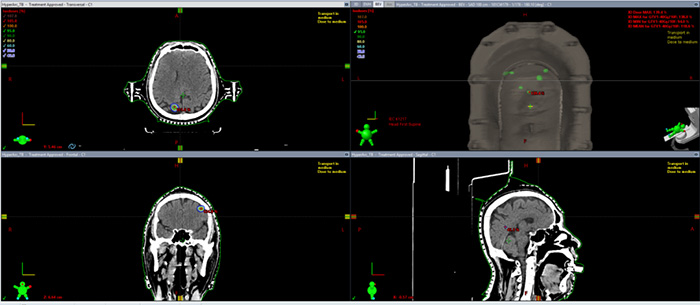

Single brain metastasis of lung cancer (1), with a prescription dose of 40Gy/10f. The clinical treatment time is about 6 minutes for CBCT and beam out treatment.

As shown in the dose distribution and DVH situation in Figures 15 and 16, the target area has good conformability, and the dose line outside the target area drops quickly. It only takes 5mm to drop to 50% of the prescribed dose.

Figure 15 Dose distribution map for Patient 2